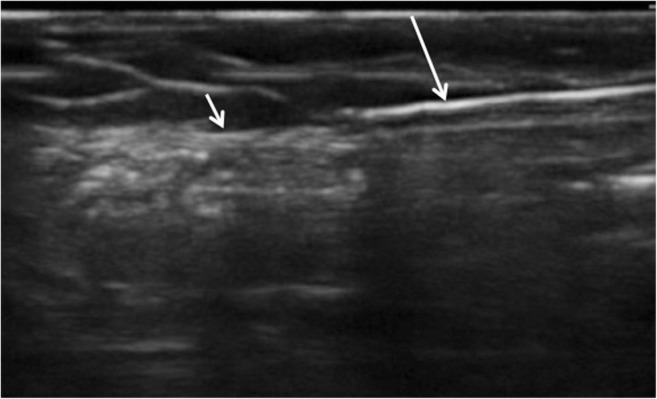

Fig. 4.

Real-time ultrasound image of blunt tunneling device (long arrow) passing immediately superficial to fascial plain (short arrow)